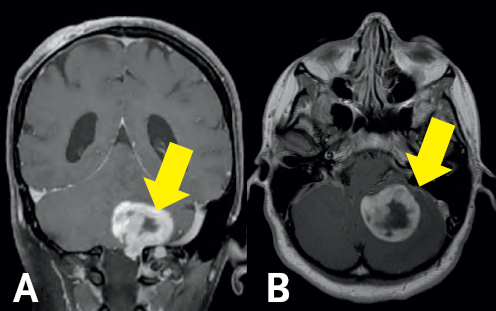

(Left) Gray colored variations are surrounded by a black and white outline. In the bottom right of the figure, there is a white blob highlighted by a yellow arrow. This blob is at the top base of a vertical dark gray column at the bottom of the image. (Right) Two dark gray spheres are conjoined at the bottom of the image. A white blob sits above the right sphere with a yellow arrow pointing towards the blob. Above the spheres are gray colored structures. All structures are enclosed by a white boarder.

FIGURE 6.1 MRI of a Glioblastoma Multiforme. Pre-operative coronal (A) and sagittal (B) MRI demonstrates a mass with central cystic areas (yellow arrows) in the left cerebellar hemisphere.

The MRI ordered by her physician demonstrated an enhancing lesion involving the intermediate zone of the left cerebellar hemisphere—suspicious for a type of malignant tumor of the brain known as a glioblastoma multiforme (GBM) (Figure 6.1).